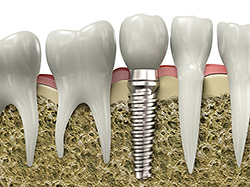

An implant is a synthetic tooth root in the shape of a post that is surgically placed into the jawbone. The “root” is usually made of titanium (the same material used in many replacement hips and knees), a metal that is well-suited to pairing with human bone. A replacement tooth is then fixed to the post. The tooth can be either permanently attached or removable. Permanent teeth are more stable and feel more like natural teeth.

The ideal candidate for an implant procedure is a non-smoker who has good oral health, including a sufficient amount of bone in the jaw and healthy gums with no sign of gum disease.